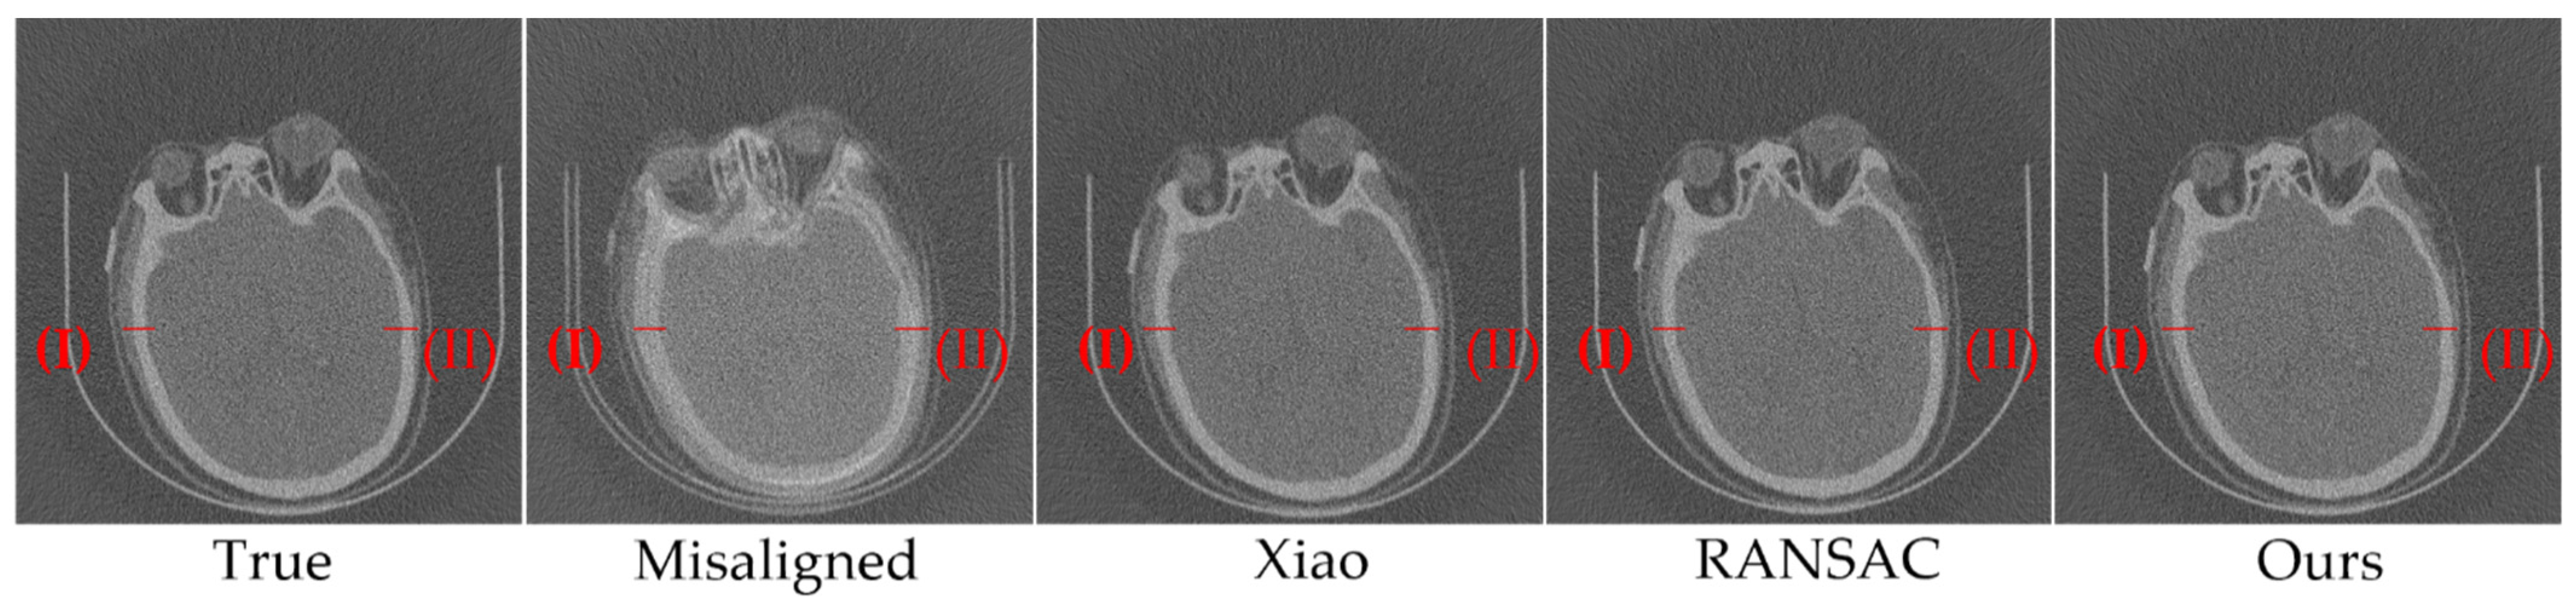

3.1. Simulation Experiments

3.2. Nanotomography Experimental Section